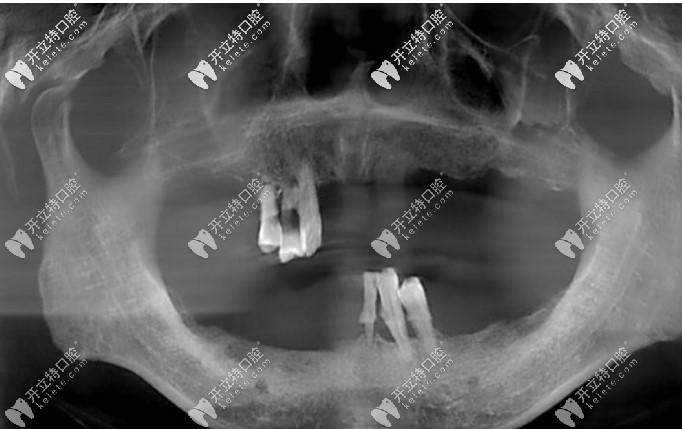

從小到大,我的牙齒中線不齊,咬合也有問題,沒想過中線不齊及咬合不好會(huì)造成臉歪等影響,只是覺得擁有滿口整齊大白牙的人笑起來都非常好看,但自己卻只能抿嘴笑,因?yàn)榭傆X得自己的牙齒不好看。

整牙前牙齒中線不齊咬合不良